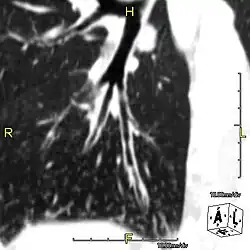

Around 80% of people with primary ciliary dyskinesia experience respiratory problems beginning within a day of birth. Many have a collapsed lobe of the lung and blood oxygen low enough to require treatment with supplemental oxygen.[1] Within the first few months of life, most develop a chronic mucus-producing cough and runny nose.[1] The main consequence of impaired ciliary function is reduced or absent mucus clearance from the lungs, and susceptibility to chronic recurrent respiratory infections, including sinusitis, bronchitis, pneumonia, and otitis media. Progressive damage to the respiratory system is common, including progressive bronchiectasis beginning in early childhood, and sinus disease (sometimes becoming severe in adults). However, diagnosis is often missed early in life despite the characteristic signs and symptoms.[2] In males, immotility of sperm can lead to infertility, although conception remains possible through the use of in vitro fertilization, there also are reported cases where sperm were able to move.[8] Trials have also shown that there is a marked reduction in fertility in females with Kartagener's syndrome due to dysfunction of the oviductal cilia.[9]

Many affected individuals experience hearing loss and show symptoms of otitis media which demonstrates variable responsiveness to the insertion of myringotomy tubes or grommets. Some patients have a poor sense of smell, which is believed to accompany high mucus production in the sinuses (although others report normal – or even acute – sensitivity to smell and taste). Clinical progression of the disease is variable, with lung transplantation required in severe cases. Susceptibility to infections can be drastically reduced by an early diagnosis. Treatment with various chest physiotherapy techniques has been observed to reduce the incidence of lung infection and to slow the progression of bronchiectasis dramatically. Aggressive treatment of sinus disease beginning at an early age is believed to slow long-term sinus damage (although this has not yet been adequately documented). Aggressive measures to enhance clearance of mucus, prevent respiratory infections, and treat bacterial superinfections have been observed to slow lung-disease progression. The predicted incidence is 1 in approximately 7500.[10]

When accompanied by the combination of situs inversus (reversal of the internal organs), chronic sinusitis, and bronchiectasis, it is known as Kartagener syndrome[3] (only 50% of primary ciliary dyskinesia cases include situs inversus).[11]